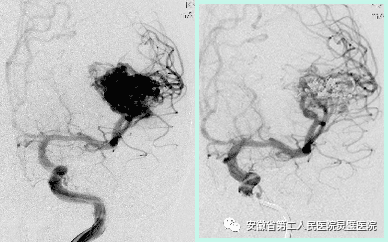

三、脑血管病的综合治疗技术

脑血管病亚专业组紧跟国际前沿,目前全面开展颅内动脉瘤、脑动静脉畸形、硬脑膜动静脉瘘等脑血管病的外科及血管内治疗,尤其对复杂颅内动脉瘤,灵活运用支架及球囊辅助、双微导管、液态栓塞剂栓塞、覆膜支架等技术,取得良好效果。开展烟雾病血管搭桥、颈内内膜剥脱术等脑血管外科手术。

手术夹闭基底动脉尖端动脉瘤

动脉瘤弹簧圈栓塞模拟过程

前交通动脉瘤术前和术后

颈内动脉动脉瘤术前和术后

动静脉瘘术前和术后

颈内动脉内膜剥脱术

烟雾病行血管搭桥+硬膜翻转+颞肌贴敷术